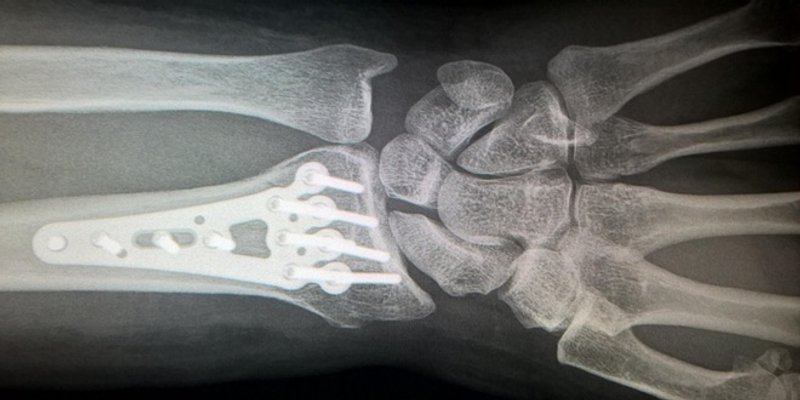

Prema njegovim riječima ljepilo može postići preciznu fiksaciju u roku od dvije do tri minute, čak i u okruženju bogatom krvlju. Ljepilo se također može prirodno apsorbirati u tijelo dok kost zacjeljuje, eliminirajući potrebu za još jednom operacijom uklanjanja implantata.

Trenutačno na tržištu postoji niz koštanih cemenata i punila za koštane šupljine za fiksiranje prijeloma, ali ni za jedan nisu utvrđena adhezivna svojstva.